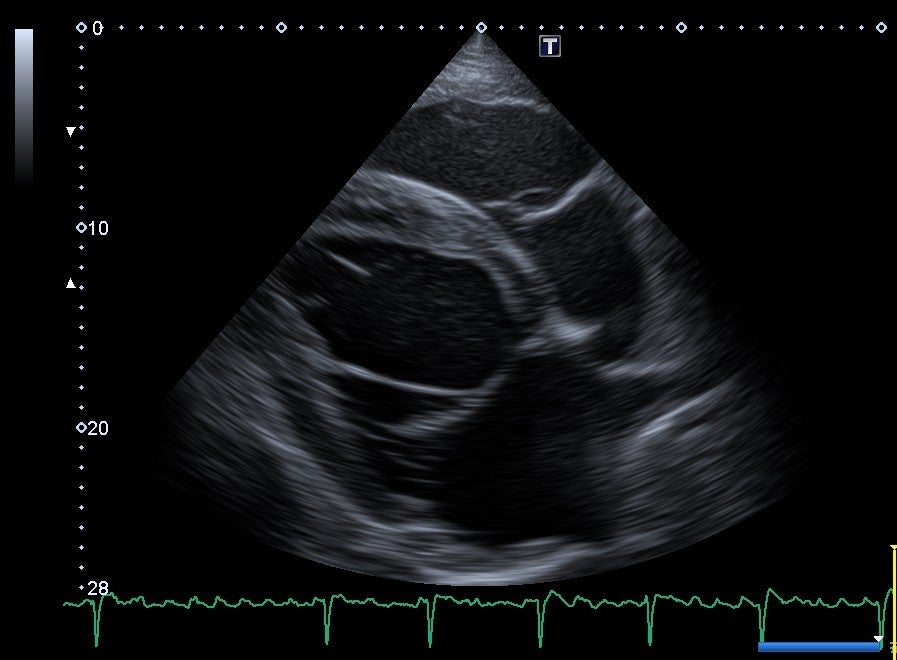

An echocardiogram, or ultrasound of the heart, is the best way to determine the cause for a heart murmur and its effects on the heart. Echocardiograms are complicated to perform and interpret. Therefore, finding a veterinarian who is specialized in equine internal medicine is ideal. Thankfully, RFEMC has an internal medicine specialist who also has advanced training in equine cardiology.